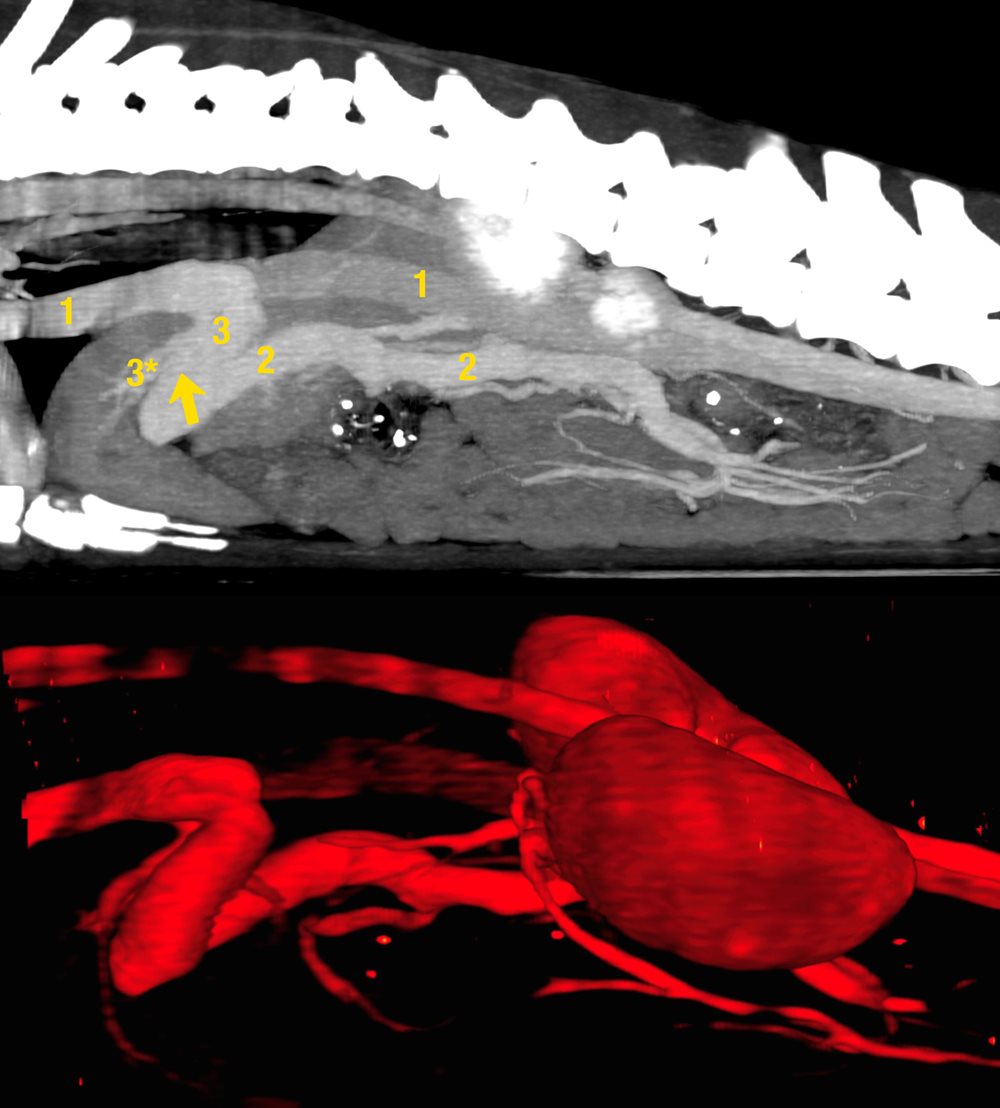

Image above: CT-Angiogram demonstrating the intrahepatic shunt which connects the portal vein with the hepatic vein and caudal vena cava.

1 Caudal Vena Cava

2 Portal Vein

Arrow location of shunt occlusion. At SCVS the Shunts are occluded at the level between the last portal branch leaving the portal vein and the first hepatic vein branch joining the hepatic vein. This technique avoids the problem of collateral shunts forming following shunt occlusion which is a problem with the stent-coil technique.

3 Hepatic vein

3* Hepatic vein branch